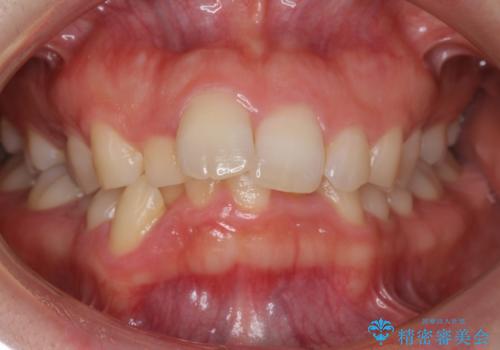

- 前歯のがたがたと出っ歯を主訴に来院。

CTを撮影したところ、臼歯部の頬側の骨の厚みが非常に大きく、通常では考えられない量の歯列の拡大が可能でした。

今回は健康を損なわずに非抜歯で治療が可能でしたが、

歯ぐきや骨の厚みが薄い他の患者さんでは難しいです。

左上5は180度捻転していましたので、そのまま並べています。